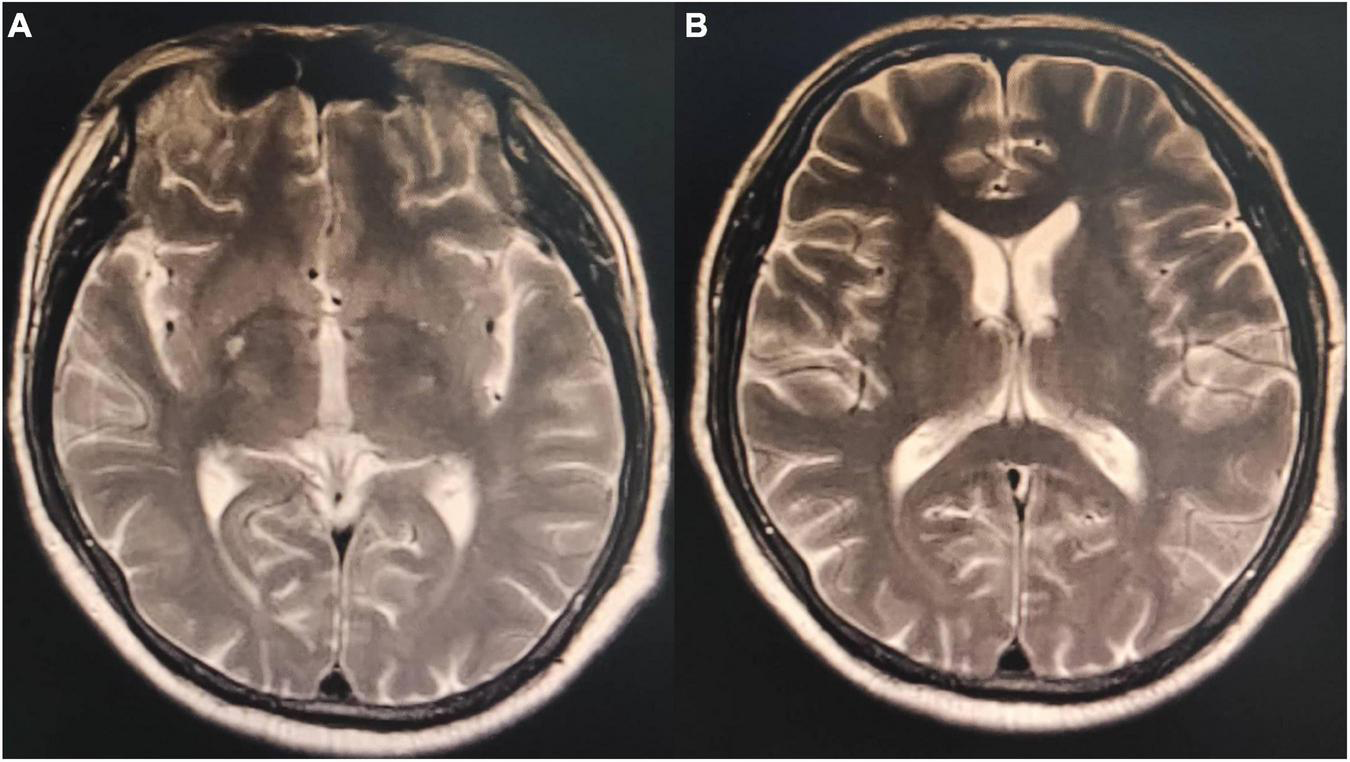

FIGURE 3

Magnetic resonance imaging T2 phase of the patient’s brain. (A) Small patches of the long T2 signal shadow in the right basal ganglia with hyperintensity in T2 fluid-attenuated inversion recovery (FLAIR) and a few patchy long T2 signals in the white matter of bilateral cerebral hemispheres with hyperintensity in T2 FLAIR. Acute lacunar infarction in the right basal ganglia might be large, and there were few ischemic degeneration foci in the white matter of the bilateral cerebral hemispheres. (B) Small patches of long T2 signal shadow were observed in the right basal ganglia, with slight hyperintensity in T2 FLAIR. A few patchy long T2 signals were observed in the white matter of the bilateral cerebral hemispheres, with hyperintensity in T2 FLAIR. A few ischemic degeneration foci in the white matter of bilateral cerebral hemispheres and ischemic infarction foci in the right basal ganglia were considered.

On admission, the patient’s temperature was 36.5°C, pulse rate was 83 beats/min, respiration rate was 21 beats/min, blood pressure was 85/65 mmHg, and oxygen saturation was 85%. He had been taking oral antihypertensive drugs for more than 10 years. However, the specific medications and control status were unknown. He has a 1 year history of cerebral infarction, with no residual limb movement disorder. He has no congenital or genetic disorders. The patient was lethargic and uncooperative during the physical examination. There was no yellowing or breaking of the skin or mucous membranes in the whole body. Cyanosis was evident in the nails. The pupils on both sides were similar in size (large) and shape (round). Moreover, no neck weakness, or resistance was observed. There was equal chest expansion, but there were weakened breath sounds in both lungs, and a small number of wet rales was heard in the middle and lower lungs. The abdomen was soft and the bowel sounds were normal. The fixed indwelling catheter revealed blue-green urine (Figure 2). No pathological reflex was elicited. Arterial blood gas examination revealed the following: pH 7.43, pCO2 39 mmHg, pO2 91 mmHg, sO2 90.0%, HCO3– 25.9 mmol/L, methemoglobin (reference value 0–3%) 11.1%, reduced hemoglobin (reference value 0–5%) 8.8%, and oxygenated hemoglobin (reference value 95–98%) 79.5%. Electrocardiogram revealed J-point depression and borderline first degree atrioventricular block (Supplementary material). Simultaneously, relevant auxiliary examinations improved (Table 1). According to the diagnostic criteria of the National Occupational Health Standards (4), the patient was diagnosed with moderate occupational acute benzene poisoning with nitro compounds. Hence, he was given dexamethasone sodium phosphate 20 mg injection followed by intravenous infusion q.d. and methylene blue 80 mg stat micropumped and maintained for 15 min. Symptomatic treatments, such as oxygen inhalation, fluid replenishment, hepatoprotective diuresis, awakening, and nutritional support were provided, and HA330 hemoperfusion therapy was administered after the vital signs had stabilized. Following treatment, the patient woke up on the same day and was able to answer questions freely. A brain CT scan revealed no abnormalities. On the 7th day of admission, he complained of dyspnea, and his oxygen saturation was maintained at 92% under oxygen inhalation. Laboratory tests revealed mild anemia and elevated bilirubin levels. Therefore, he was administered a polysaccharide iron complex capsule 0.15 g orally q.d. Magnetic resonance imaging (MRI) of the brain revealed a possible acute lacunar infarction in the right basal ganglia and a few ischemic degenerations in the white matter of both hemispheres (Figure 3). On the 11th day of admission, the patient’s breathlessness had not improved significantly, and arterial blood gas revealed 8.1% methemoglobin, pH 7.42, pCO2 45 mmHg, pO2 100 mmHg, sO2 97.7%, and HCO3– 29.2 mmol/L. Subsequently, 20 mg of methylene blue was administered and maintained via micropump for 15 min b.i.d. Additionally, an intravenous infusion of 3.0 g of vitamin C q.d. was administered. After treatment, the patient’s condition gradually improved, and he was discharged from the hospital on September 4, 2022. The patient was instructed to do regular follow-up after discharge. However, due to the novel coronavirus epidemic, the patient did not return to our hospital. One month after discharge, our department made a telephone follow-up and the patient complained of weakness but had no episode of suffocation. Three months after discharge, the patient reported that he had no discomfort and had good quality of life.

Nitrobenzene is an oxidizing nitrite compound (5) that can cause human poisoning when 35 mg/kg is absorbed. The skin absorbs nitrobenzene at 2 mg/(cm2⋅h) rate. Moreover, nitrobenzene vapor can be absorbed via the skin and respiratory tract simultaneously, with a total retention rate in the body reaching 80% (6). Methemoglobinemia caused by nitrobenzene poisoning is the main pathological basis of acute poisoning. The intermediate substance formed during its biological transformation in the body causes red blood cell rupture and hemolysis. After entering the human body, nitrobenzene is transformed to produce intermediate products, which can lead to the reduction of reduced glutathione. Reduced glutathione plays an important role in the survival of red blood cells, such as in the maintenance of the normal function of red blood cell membrane. When reduced glutathione is decreased, it is easy to cause hemolysis. The intermediates also directly act on the basophobia in globin molecules to promote denaturation. The denatured globin condenses into precipitates and forms inclusion bodies (Hearn corpuscles) in red blood cells. The red blood cells containing Hearn corpuscles are easily ruptured, which is another reason for hemolysis. The red blood cell count decreases rapidly within 3-4 days but gradually increases after 1-2 weeks with active treatment. Furthermore, nitrobenzene poisoning can cause liver and kidney dysfunction, which usually occurs 2–3 days after the poisoning. Other symptoms include cardiogenic pulmonary edema and multiple organ dysfunction (7). The neurological symptoms of nitrobenzene poisoning are apparent, with excitation symptoms such as dizziness, headache, lethargy, and coma occurring earlier. The initial symptoms of the patient were obvious, which included high fever in the summer, acute attack after several hours of skin exposure, loss of consciousness, coma, and lip cyanosis. The patient had a history of cerebral infarction, but no obvious neurological symptoms occurred during hospitalization. Moreover, no abnormalities were observed in the early brain CT. However, MRI revealed right basal ganglia and bilateral white matter lesions 7 days after admission, indicating toxic encephalopathy caused by nitrobenzene poisoning. Current neurologic symptoms (headache, confusion, and coma) after nitrobenzene poisoning are usually interpreted as methemoglobinemia complications from the resulting cerebral hypoxia. However, some studies suggested that CT and MRI reveal targeted brain lesions rather than hypoxic encephalopathy. Moreover, toxic encephalopathy occurs more in the cerebellum and brainstem, and most of the lesion sites are symmetrically distributed (8). However, other sites cannot be excluded.